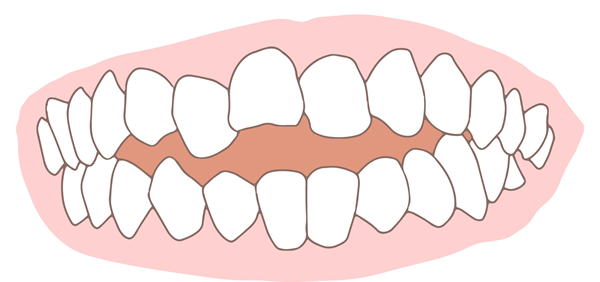

開咬(浅い噛み合わせ)

奥歯は噛み合っていますが、前歯は噛み合っていない状態です。その結果、奥歯に大きな負担がかかります。